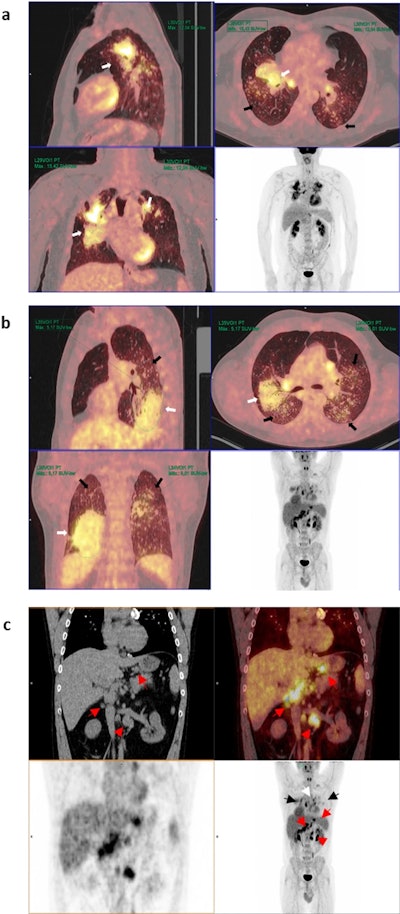

Representative PET/CT images from patients with: (a) high and (b) low SUVmax values and (c) hypermetabolic lymphadenopathy in other extrathoracic areas. (a) Maximum intensity projection (MIP) PET images (bottom right) and sagittal, axial and coronal and PET/CT images of a patient with bilateral pulmonary heterogeneous condensations (white arrows) showing intense metabolic activity up to an SUVmax of 15.42 in the right upper lobe, as well as scattered millimetric nodules (black arrows). (b) MIP PET images and in the sagittal, axial and coronal PET/CT images showing bilateral pulmonary condensations, which are larger on the right side (white arrows), and numerous bilateral millimeter-sized nodules (black arrows). Slight diffuse and heterogeneous increased uptake (up to an SUVmax of 5.17) is observed, even in areas of apparently healthy lung parenchyma. (c) PET, CT, and PET/CT images in coronal and MIP sections in which, in addition to bilateral pulmonary (black arrows) and mediastinal (white arrow) involvement, multiple abdominal lymphadenopathies are observed in the celiac space, gastrohepatic ligament, and retroperitoneum (red arrows), even below the renal artery (red arrowhead).Representative PET/CT images from patients with: (a) high and (b) low SUVmax values and (c) hypermetabolic lymphadenopathy in other extrathoracic areas. (a) Maximum intensity projection (MIP) PET images (bottom right) and sagittal, axial and coronal and PET/CT images of a patient with bilateral pulmonary heterogeneous condensations (white arrows) showing intense metabolic activity up to an SUVmax of 15.42 in the right upper lobe, as well as scattered millimetric nodules (black arrows). (b) MIP PET images and in the sagittal, axial and coronal PET/CT images showing bilateral pulmonary condensations, which are larger on the right side (white arrows), and numerous bilateral millimeter-sized nodules (black arrows). Slight diffuse and heterogeneous increased uptake (up to an SUVmax of 5.17) is observed, even in areas of apparently healthy lung parenchyma. (c) PET, CT, and PET/CT images in coronal and MIP sections in which, in addition to bilateral pulmonary (black arrows) and mediastinal (white arrow) involvement, multiple abdominal lymphadenopathies are observed in the celiac space, gastrohepatic ligament, and retroperitoneum (red arrows), even below the renal artery (red arrowhead).Scientific Reports

According to the analysis, the average maximum standardized uptake value (SUVmax) of large opacities was 6.32 ± 3. All of the patients demonstrated hypermetabolic mediastinal lymphadenopathies, and 88.2% of the patients also demonstrated extrathoracic lymphadenopathies.